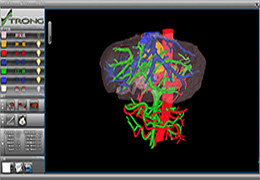

Diffusor Tension Imaging (DTI) module to analyze diffusion-weighted MRI data including calculation of FA maps, fiber tracking and FA group comparisons.

Visualization Tools

Parametric and non-parametric statistical maps may be superimposed both on the original functional scans as well as onto T1-weighted 2D or 3D anatomical reference scans. Time courses of selected regions-of-interest (ROIs) are available both in 2D and 3D representations. Statistical maps may be computed either in the 2D or 3D representation since structural as well as functional 4D data (space x time) are transformed into Talairach space. This allows you to compare activated brain regions across different experiments and across different subjects

The surface reconstruction procedure starts with a sphere (recursively tesselated icosahedron) or a rectangle, which slowly wraps around a (segmented) volume data set. In order to avoid topological defects and to let the surface smoothly grow into deep sulci, a dynamic mesh algorithm was developed which automatically invents new polygons on the fly at places where they are needed. A reconstructed cortical surface may be inflated, cut interactively and slowly unfolded minimizing areal distortions. Statistical 3D maps may be superimposed on reconstructed, inflated or flattened cortex. Signal time courses may be invoked by simply pointing to any region of a visualized surface.